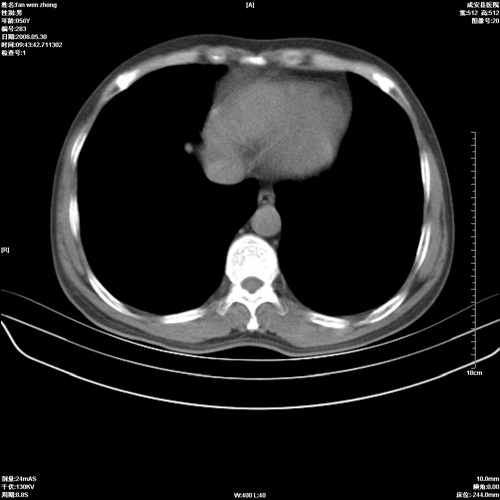

病人 男 56岁 一周前高热,体温达39-40度,经抗炎治疗后,体温渐降,达37,5-38度,轻微咳嗽,胸部不适 查白细胞为1.3万 行ct检查,请分析。

双肺内可见多发结节状病灶,并见小空洞,病人高热,白血球增高,应该是典型的迁徙性肺脓肿(多为金黄色葡萄球菌感染)。查一下口腔等其它部位有无感染灶。

双肺内可见多发结节状病灶,并见小空洞,病人高热,白血球增高,应该是典型的迁徙性肺脓肿(多为金黄色葡萄球菌感染)。建议治疗后复查.